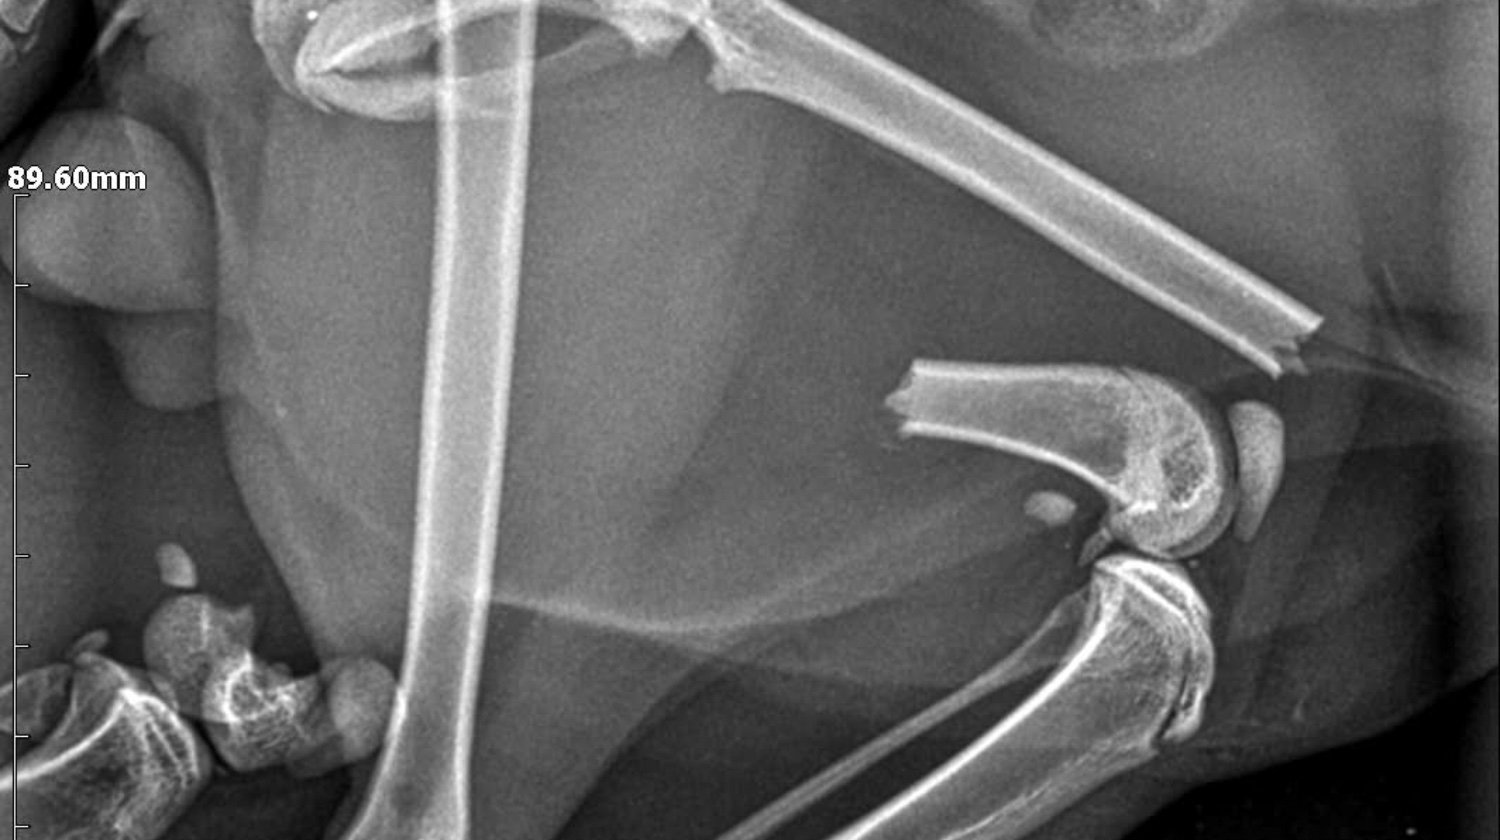

Lucky je maček, ki so ga pred nekaj dnevi našli pred blokom, v katerem živi moj brat. Luckyja je takoj odpeljal k veterinarju. Po posvetu je ugotovil, da ima poškodovani obe nogi in medenico :(. Natančneje, ima naslednje težave:

Medenica

obojestranska sakroiliakalna dismoreksija

Zlom desne iliakalke s premikom

Zadnje okončine

Diafizni zlom v srednji tretjini, poševni, s premikom, brez kostne eklatantnosti, na ravni stegnenice femurulolistangii

Zlom tipa SH I distalno od desne stegnenice

Slikovna diagnoza: zlom leve stegnenice, SH zlom desne stegnenice, obojestranski križno-iliakalni izpah, zlom desne iliakalne palete

Po opravljenih rentgenskih posnetkih, kjer so bile ugotovljene

zgoraj, so ga odpeljali k ortopedu in bo potreboval 3 operacije: po eno za vsako nogo + operacijo medenice.